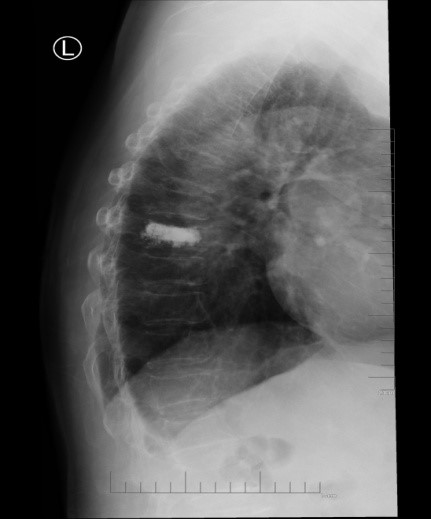

吴老太太今年86岁,同时患有心脏病、老慢支、哮喘、糖尿病等多种疾病,不久前因为并发心衰、呼衰在独墅湖医院经抢救后脱离危险。然而不巧的是,几天前自己在家只轻轻扭了一下腰,就感觉背部疼痛难忍,寝食难安。于是来到我院骨科就诊,医生怀疑是脊柱骨质疏松性骨折,安排收治住院,对病患进行磁共振检查后证实是“第8胸椎压缩性骨折”。

医生在诊断后决定行经皮椎体后突成形术(简称PKP术),需要病人在全身麻醉下俯卧位,医生在全程透视下完成手术。对于一般的患者来说不成问题,而对吴老太太而言却难以实施。首先,她的全身情况较差,心肺功能不全,基础疾病多且严重。入院时就有明显的呼吸困难,氧饱和度只有70%左右,很难耐受全身麻醉。即使勉强度过手术阶段,术后也可能要气管插管,靠呼吸机维持生命,肺部感染则难以控制。其次,如果采用局部麻醉俯卧位手术,尽管可以规避全麻的风险,但该患者根本不能承受俯卧位对心肺功能的影响。但如果不采取手术,卧床以及日夜不停的疼痛对已经遭受过心衰和呼衰的吴老太太来说是雪上加霜。

在常规办法难以实施时,独墅湖医院骨科的医生们决定另辟蹊径,挽救病患生命。常规手术主要面临两大难题:全身麻醉与俯卧位。那么如果采用局部麻醉与侧卧位呢?对!这就是解决问题的关键!局麻可以规避全麻的风险;侧卧可以避免俯卧对心肺的影响。如此,问题似乎迎刃而解了。但是,这样的改变,尤其是侧卧位完成PKP术,导致空间位置变了,手术的难度大大增加了。而且,吴老太太耳背,局麻侧卧位手术需要病人的配合,术中的沟通也是一个问题。尽管困难重重,这也是挽救老人家生命的唯一可行的办法。

在与家属充分沟通后,3月11日上午,骨科姜为民主任亲自披挂上阵,杨小海主任医师等团队成员紧密配合,一切按计划进行。然而,刚开始消毒,预料中的问题出现了:患者开始扭动身体,又无法有效沟通,如此手术将难以继续下去。好在姜主任团队早有预案:静脉适量给药镇静。在麻醉科侯永恒副主任的密切配合下,患者恢复了平静,各项生命指标平稳。姜主任凭借高超的手术技巧,仅用25分钟即高质量地完成了这例非常规手术。